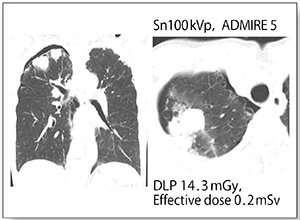

症例4は,原発性肺がん疑いで当センターにて肺生検を施行し,翌日にTin filterプロトコルで気胸のフォローアップ撮影を行った。胸部単純X線を数枚撮影した程度の線量で明瞭な画像を得られている(図4)。現在当センターでは,肺生検後のフォローアップはすべてSOMATOM DriveのTin filterプロトコルで実施している。

図4 症例4:原発性肺がん疑いで肺生検施行後

(60歳,女性)